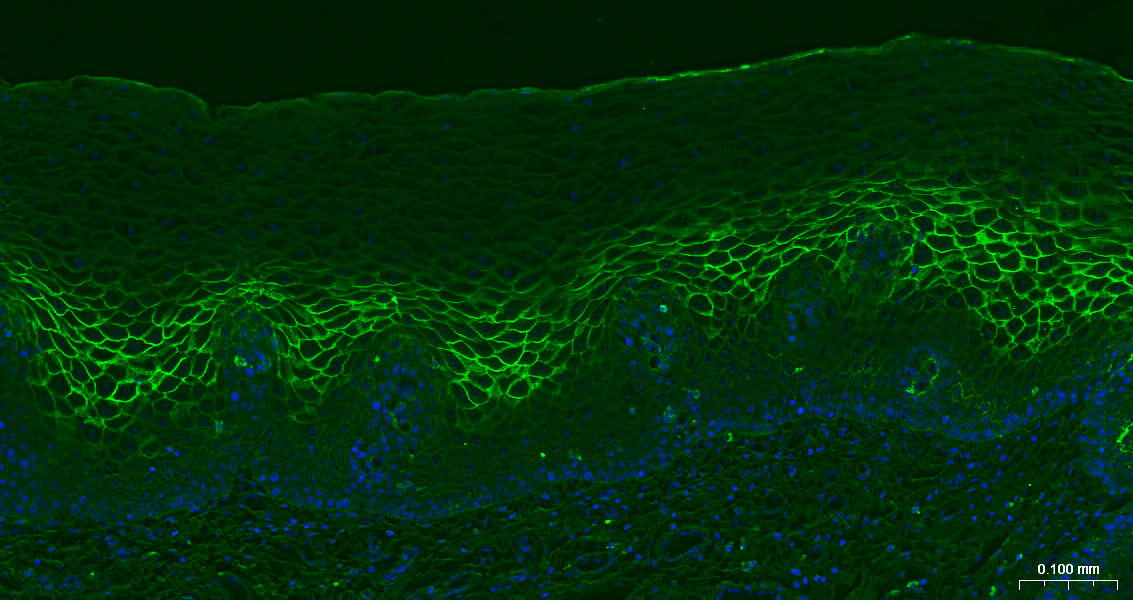

Paraformaldehyde-fixed, paraffin embedded Human Esophagus; Antigen retrieval by boiling in sodium citrate buffer (pH6.0) for 15 min; The section was incubated with CD138 Monoclonal Antibody, Unconjugated (bsm-60902R) at 1:200 overnight at 4°C. Followed by conjugated Goat Anti-Ratbbit IgG antibody (green, bs-0295G-BF488), DAPI (blue, C02-04002) was used to stain the cell nuclei.